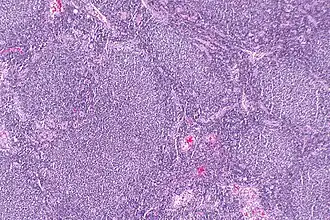

![]() Микрофотография фолликулярной лимфомы, показывающая характерно аномальные лимфоидные фолликулы, которые дали заболеванию название. Пятно H&E. | |

Опухоль состоит из фолликул, состоящих из смеси центроцитов (Кильская терминология, принятая экспертами ВОЗ) или расщеплённых клеток фолликулярного центра (старая американская терминология), «маленьких клеток», а также центробластов (Кильская терминология) или большие нерасщеплённые клетки фолликулярного центра и «больших клеток». Эти фолликулы окружены незлокачественными клетками, в основном T-клетками. В фолликулах, обычно преобладают центроциты. Центробласты, как правило, в меньшинстве.